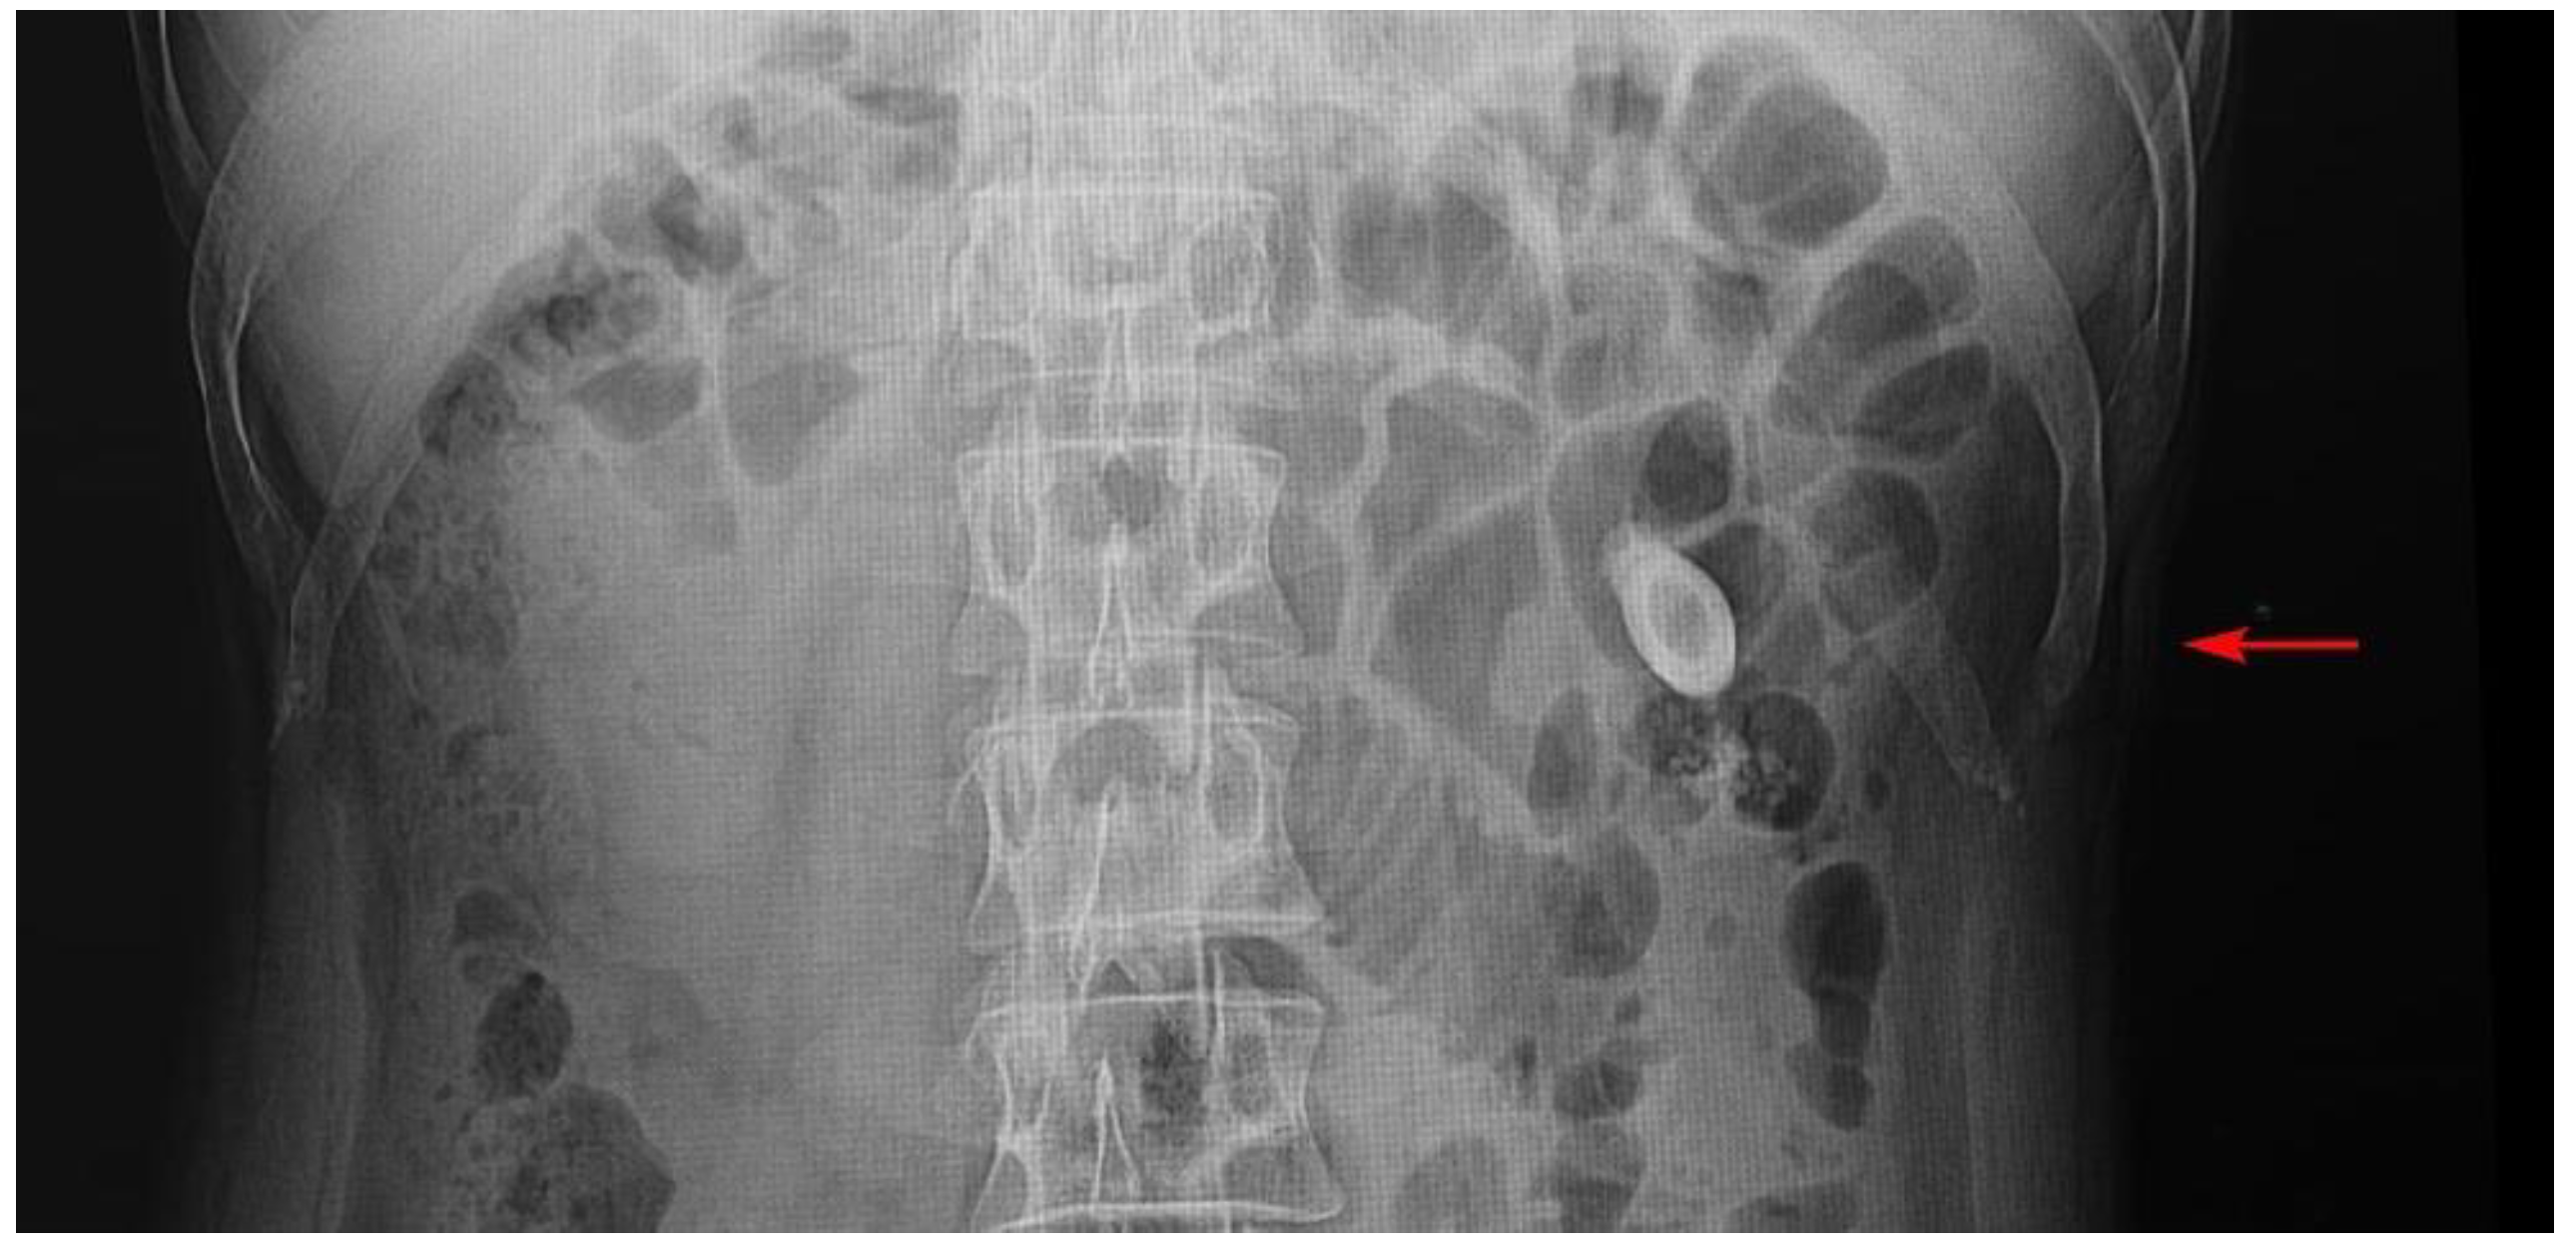

His ureteric calculus was removed two weeks following his episode of urosepsis and he was followed up at the urology clinic. The ureteric calculus was sterile following microbiology cultures and 16s DNA analysis. For about one year after the episode of pyelonephritis, he has not had urinary tract infections (Figure 2).

Figure 2. Timeline of the management of a patient with Actinotignum schaalii pyelonephritis following ureteric calculus.